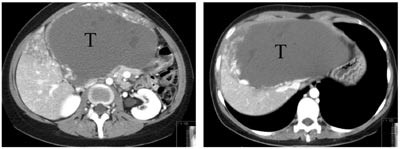

Pasient 1. 64 år gammel mann som ble utredet ved lokalsykehus for ukarakteristiske magesmerter. Ved abdominal CT var det blitt påvist en 6 x 6 x7 cm stor tumor beliggende mot leverens bakside, muligvis i segment 1. V. cava var sterkt komprimert og på det nærmeste okkludert av denne tumoren (fig 1). Tumoren ble initialt oppfattet som et leverneoplasme. Grunnet relasjonen til v. cava ble tilstanden ansett som utilgjengelig for kirurgi, men pasienten ble henvist til Rikshospitalets Seksjon for gastroenterologisk kirurgi til vurdering (second opinion). Biopsimateriale fra tumoren ble av ett laboratorium med et visst forbehold beskrevet å være fra et leiomyom. Et annet laboratorium mente det dreide seg om et schwannom. Antatt risiko for forestående okklusjon av vitale leverkar samt en sannsynlighet for at det dreide seg om et malignt neoplasme gjorde at man ble enig om å forsøke kirurgisk fjerning av tumor. Rutinemessige preoperative blodprøver viste normale verdier (e-tab 1).

Pasient 2. 29 år gammel kvinne som de siste tre år hadde merket økende bukomfang og ubehag i abdomen. Hun hadde gjentatte ganger konsultert lege for dette før hun ble innlagt i lokalsykehus til utredning for anemi. Det ble der konstatert at pasienten hadde en meget stor levertumor, hvorpå hun ble overflyttet til Rikshospitalet. Hun hadde da et bukomfang som ved langtkommet graviditet. Nedre kant av tumor kunne palperes nedenfor umbilicus. CT (fig 5) viste at det dreide seg om en ekstremt stor levertumor, et sannsynlig hemangiom, som inntok hele venstre leverlapp, inkludert segment 4. Høyre leverlapp var flatklemt ut mot flanken. Den retrohepatiske del av v. cava var tilsynelatende okkludert, og et utstrakt nett av kollateraler ble påvist. Preoperative laboratorieprøver er vist i e-tabell 2.